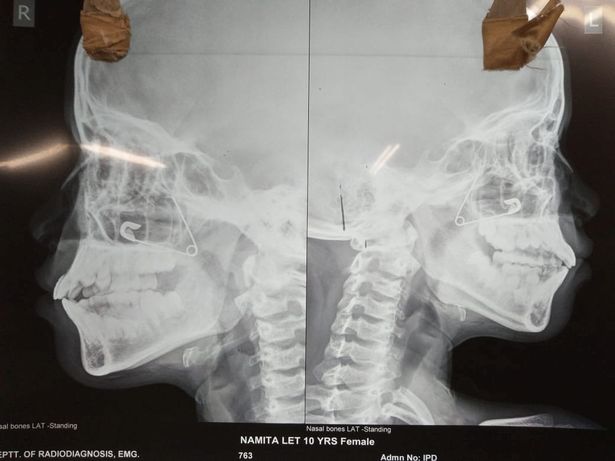

Hình ảnh chiếc kim băng đang mắc kẹt trong mũi cô bé Ấn Độ. Ảnh: Mirror

Bác sĩ Suvendu Bhattacharya tại bệnh viện cho biết: “Đứa trẻ được đưa đến bệnh viện của chúng tôi vào khoảng 5 giờ chiều với cơn đau dữ dội và liên tục chảy máu mũi. Tôi đã chụp x-quang cho cô bé và thông báo vấn đề cho bố mẹ của em”.